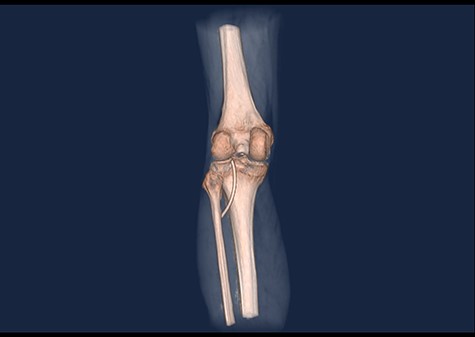

A 61-year-old male patient was diagnosed with inoperable stomach cancer. A TIVAD of the type Braun Celsite ST301® was inserted in the right subclavian vein for administration of chemotherapy. Location was confirmed by chest X-ray and the TIVAD was reported functioning with good backflow (Fig. 1). During initiation of the chemotherapy treatment, the TIVAD was reported malfunctioning. Contrast X-ray showed fibrin sheaths at the distal end of the catheter. An endovascular procedure was performed by an interventional radiologist and fibrin sheaths were mechanically removed with a snare (Fig. 2). Intraoperative X-ray with contrast showed normal contrast accumulation distal to the catheter tip and the patient received the first dose of chemotherapy. One month later the patient was hospitalized with bilateral pulmonary thromboembolism. The patient was treated with low-molecular-weight-heparin and discharged. The chemotherapy treatment continued as scheduled, with one pause due to a fracture of the right humerus after a fall. Occasionally, the TIVAD was malfunctioning and medication was administered using a peripheral venous catheter. During a planned pause in treatment, the patient sought hospital care due to worsening of his general condition. CT showed progress of malignancy and another round of chemotherapy was initiated and administrated using the TIVAD without any problems. Less than a week after, the patient reported feeling a tender swelling underneath his left foot. Ultrasound showed no DVT. The swelling and tenderness disappeared spontaneously, but the patient reported brief incidents of pain under his left foot. A CT scan was performed the next time the TIVAD did not function, showing that the distal 8 cm of the catheter was missing. The patient had no symptoms and reported no discomfort of any kind. The TIVAD was removed, confirming a fracture. A chest CT showed no foreign bodies. A full-body CT scan without contrast was performed, revealing the missing catheter part located at the level of the left knee (Figs 3 and 4). Vascular surgeons performed an endovascular procedure through the femoral vein assuming the catheter had embolized to the popliteal vein. Contrast examination revealed no catheter in the vein and another approach through the femoral artery was made, where contrast imaging shows that the catheter was, in fact, located in the popliteal artery (Fig. 5). The catheter, measuring 7.5 cm, was successfully removed with the use of a snare without any complications. The patient was discharged from hospital and referred to a diagnostic echocardiogram (Fig. 6). A bubble echocardiogram was performed to detect an atrial septal defect but was unsuccessful in doing so. For a final diagnosis, the patient was recommended a transesophageal echocardiogram, but as the diagnosis would not alter the course of treatment, the patient declined further examinations. Except for the reported episodes of pain and swelling of the left foot, the patient suffered no injury and finished his chemotherapy treatment.

3D CT scan showing posteroanterior view with catheter embolus in the level of the left knee.